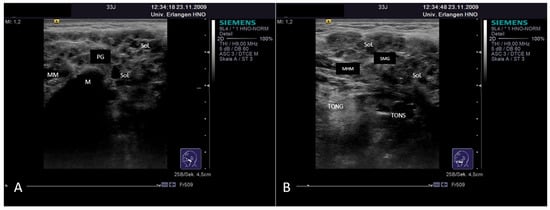

3.4.2. Chronic Recurrent Juvenile Parotitis

3.4.3. Sjoegren’s Syndrome/Disease